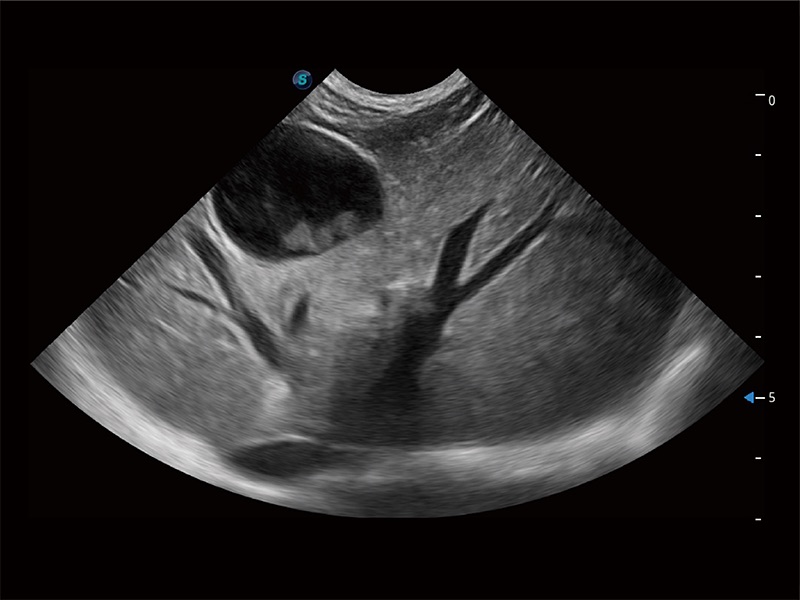

高性能和先进的临床应用工具可以为动物医生提供临床信心。ProPet 80 搭载了先进的腹部和浅表应用工具,帮助医生在日常临床实践中发挥前所未有的作用。

ProPet 80 配备了丰富的心脏探头群、先进的成像技术和专业的心脏测量工具,可帮助动物医生为不同体型和生理结构的动物提供心脏和心肌功能的全面评估。